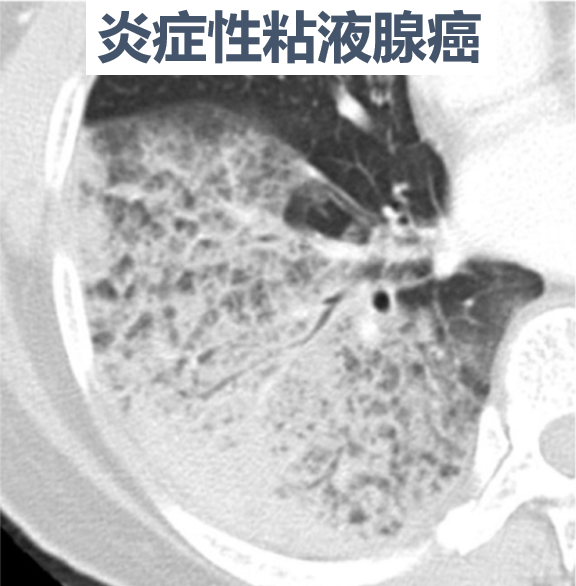

80.8%的广泛型肺炎患者,是粘液腺癌。

图片

前面提到,那些广泛型肺炎类肺癌中,有80%是粘液腺癌。

但是,并非所有粘液腺癌,都表现为肺炎。

它们也可能表现为一些孤立性肺结节。